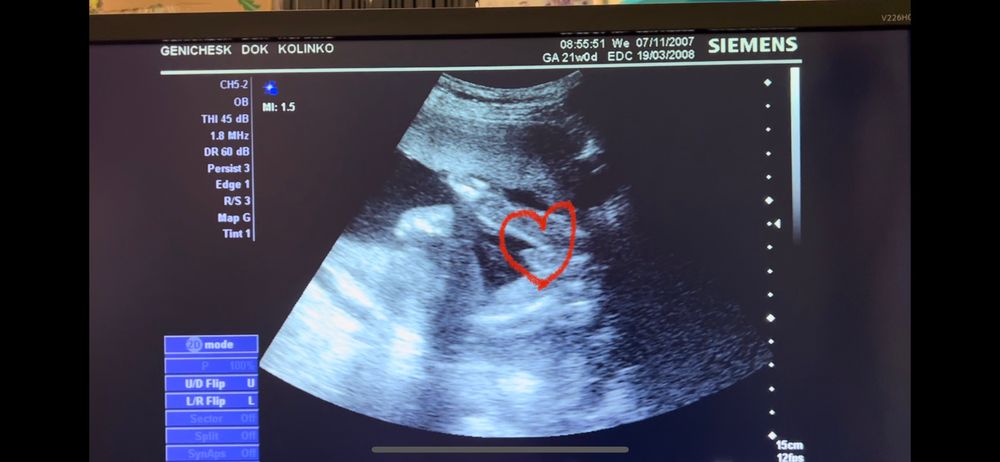

Пол малыша

У нас будет сын! Муж очень рад , будет у него мужская компания в семье ) говорил если будет еще доча ,то заведет себе кота🤣

Это все конечно шуточки , мы просто рады что по анализам и узи все хорошо! Наш малыш - крепыш💓